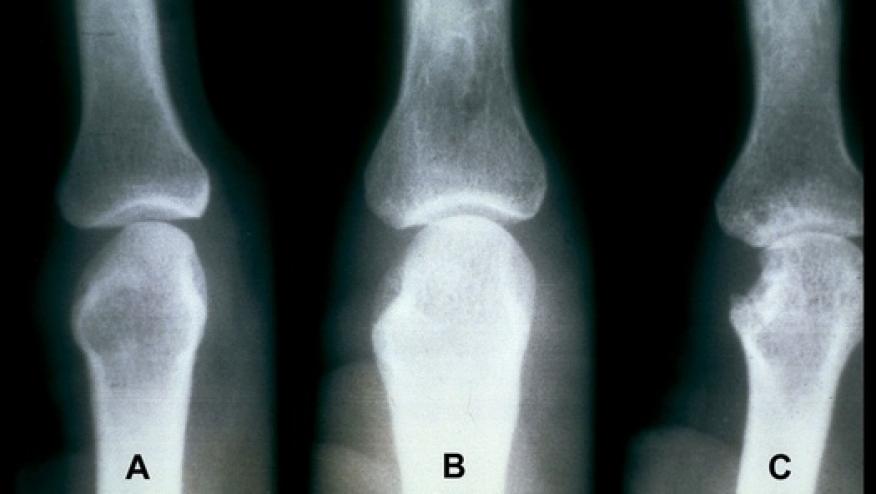

JAK inhibitors have been shown in clinical trials to retard the development of bone erosions while controlling RA inflammation and other clinical features.

They postulate that the use of JAK inhibitors in humans with RA may have bone-anabolic effects and further the effort to protect against bony erosions - partly based on their ability to increase osteoblast function and bone formation.